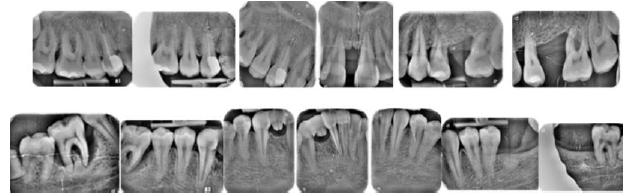

Lâexamen exobuccal Ă©tait sans particularitĂ©s. Lâexamen endobuccal a objectivĂ© une inflammation marginale modĂ©rĂ©e Ă sĂ©vĂšre gĂ©nĂ©ralisĂ©e avec un indice dâOleary Ă 68%, un indice gingival (BoP = Bleeding on Probing) Ă 76%, et un trama occlusal sur 42 (Figure 1). Le bilan parodontal montre des sites avec une profondeur de sondage (PS) de 12mm, et plus de 50% des dents prĂ©sentant une perte dâattache â„ 5mm. Le bilan radiographique a montrĂ© des pertes osseuses terminales, avec un rapport perte osseuse/Ăąge Ă 4,5 (Figure 1)

Le diagnostic de parodontite stade IV grade C généralisé a été proposé (1), avec un pronostic irrationnel au traitement pour les dents 25, 36, 42 et défavorable pour 11, 21, 35, 46 (2).

La thĂ©rapeutique Ă©tiologique a consistĂ© en une Ă©ducation Ă lâhygiĂšne bucco-dentaire, une Ă©limination des facteurs de rĂ©tention de plaque, lâextraction 42+rĂ©section radiculaire et rĂ©alisation dâune contention en fibre de verre avec la couronne ; dâune instrumentation non chirurgicale supra et sous gingivale

par quadrant (3) combinĂ©e Ă une antibiothĂ©rapie (3,4). Une chirurgie avec lambeau dâaccĂšs selon la technique du lambeau avec incision intrasulculaire (open flap) a Ă©tĂ© rĂ©alisĂ©e sur la 46. Une thĂ©rapie parodontale de soutien associĂ©e Ă une phase correctrice a Ă©tĂ© mise en place aprĂšs la thĂ©rapie parodontale active (5). La rĂ©habilitation orale a consistĂ© dans un premier temps Ă rĂ©aliser une correction orthodontique (Figure 2) ; et dans un second temps la conception dâune Ă©pithĂšse gingivale (Figure 3)

AprĂšs 6 mois, pas de profondeurs de poches â„ 6mm, avec un indice de plaque Ă 9% et un indice gingival < 10%. La thĂ©rapeutique non chirurgicale a permis un gain dâattache

stable qui sâest traduit par une diminution des profondeurs de sondage en regard de la 11, 21, et 36 dont le pronostic Ă©tait dĂ©favorable, mais aussi lâapparition dâimportantes rĂ©cessions postthĂ©rapeutique (Figure 4). La chirurgie avec lambeau dâaccĂšs a permis Ă©galement dâamĂ©liorer le niveau osseux de la 46. Le pronostic gĂ©nĂ©ral Ă long terme de la patiente a Ă©tĂ© amĂ©liorĂ©.